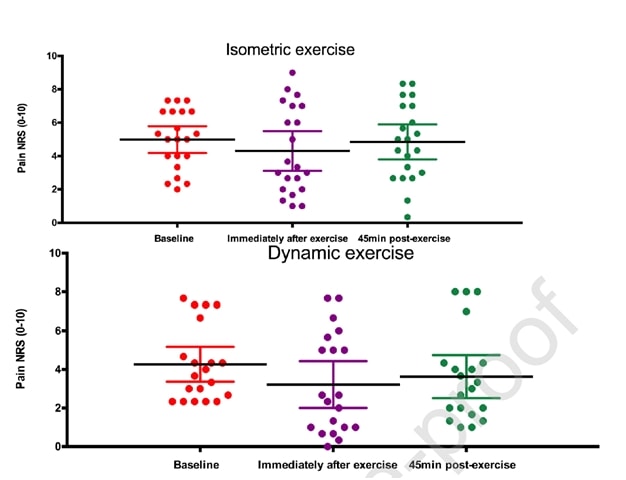

Dieselben Autoren führten zwei Jahre später eine Folgestudie mit springenden Athleten durch (Rio et al. 2017), in der sie ein isometrisches Programm und ein isotonisches Programm miteinander verglichen. In dieser Studie waren die Ergebnisse bei beiden Gruppen etwas uneinheitlicher, wobei die isometrische Gruppe eine stärkere unmittelbare Schmerzlinderung verzeichnete:

Eine aktuelle Studie von Holden et al. (2019) untersuchten ebenfalls die Wirkung von Isometrics bei Patellarsehnenentzündung und fanden keine schmerzlindernde Wirkung:

Abbildung aus Holden et al. (2019)

Der hohe Frauenanteil und das relativ hohe Durchschnittsalter sind jedoch untypisch für die Patellarsehnenerkrankung, die normalerweise eine Erkrankung junger, springender Männer ist. Es könnte also sein, dass die Diagnose einer Patellarsehnenerkrankung in einigen Fällen nicht korrekt war. Diese beiden Studien wurden zwar für die Patellarsehnenerkrankung durchgeführt, aber wir sollten prüfen, ob sich diese Ergebnisse auch auf andere Sehnen übertragen lassen.